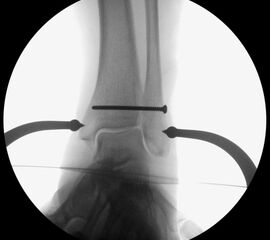

Die eigentliche Reposition der Syndesmose erfolgt mittels einer Repositionszange über dem Malleolus medialis und lateralis, entlang der Achse des oberen Sprunggelenkes und wird nach Reposition in anatomischer Stellung fixiert 52. Dabei ist auf eine Neutralstellung im oberen Sprunggelenk zu achten. Die temporäre Fixierung des DTFG kann mittels Schraube(n) oder einem dynamischen System (Suture Button - z.B. Tight-Rope, Fa. Arthrex™) erfolgen. Bei der Fixierung mittels Schraube können eine oder zwei Schrauben von 3,5-4,5 mm Stärke, tri- oder quadricortical, verwendet werden 53. Dies werden am posterolateralen Rand der Fibula in leicht aufsteigender Technik (30°), circa 2 cm und 3,5 cm oberhalb der tibiotalaren Gelenkfläche, parallel zur OSG-Achse nach entsprechendem Vorbohren eingebracht. Eine Schraubenpositionierung 2 cm oberhalb der tibiotalaren Gelenkfläche konnte in biomechanischen Untersuchungen eine bessere biomechanische Stabilität des DTFG gewährleisten als eine Positionierung der Schraube weiter proximal 54. Keinen Vorteil gegenüber tricortical eingebrachten Stellschrauben wiesen dagegen Schrauben auf, welche vier Corticalices fassen 55. Ob eine Entfernung der Syndesmosenstellschraube sinnvoll ist oder nicht, ist bist heute Bestandteil der internationalen Diskussion 56. Wir Entfernen Stellschrauben nach ca. 6 Wochen bei erhaltenem PITFL, sind alle Syndesmosenbänder verletzt, wird die Stellschraube 8 Wochen belassen.